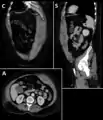

Rectus sheath hematoma seen on axial CT – with active bleeding under Marcoumar- Rectus sheath hematoma as seen on ultrasound[2]